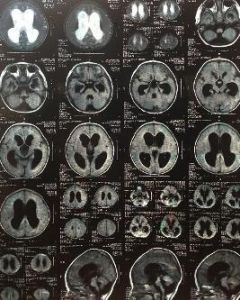

(2)CT、MRI檢查: 病變早期CT或顱腦MRI檢查可正常,有神經系統併發症時可見腦室擴大、腦溝變窄、腦腫脹腦移位等異常表現。並可發現室管膜炎、硬膜下積液及局限性腦膿腫。增強MRI掃描對診斷腦膜炎比增強CT掃描敏感,增強MRI掃描時能顯示腦膜滲出和皮質反應。採取合適的技術條件,能顯示靜脈閉塞和相應部位的梗死。